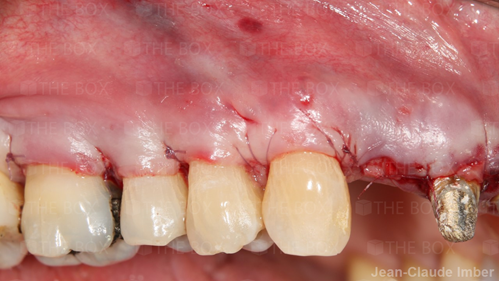

A new case was made public by Jean-Claude Imber check it out here.